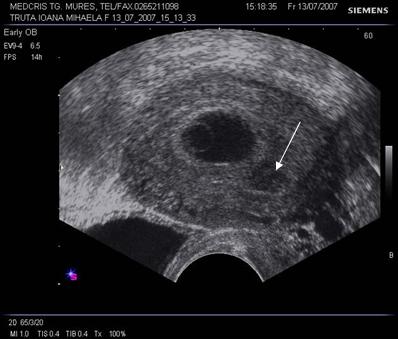

Oul clar este definit ca o sarcina anembrionata si fara sac Yolk (cca 1/3 din avorturile spontane) [10].

Incidenta anomaliilor cromozomiale este mai mare decat la avorturile cu embrion prezent, in special a trisomiilor. Ecografia transvaginala va indica un sac gestational gol, a carui marime este corespunzatoare relativ la durata amenoreei, eventual cu usor contur neregulat.

Pentru a nu face o eroare de diagnostic in prezenta unui sac gestational prea mic , posibil al unei sarcini incipiente, o reevaluare la o saptamana va fi necesara.

Fig. nr. 82 Ou clar la ecografia transvaginala